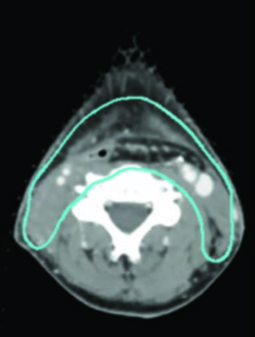

La experiencia del Memorial Sloan Kettering Cancer Center ilustra la aplicación práctica de estos volúmenes. En un caso T2N0 de seno piriforme izquierdo, el PET/TC reveló lesión captante extendiéndose hasta la línea media con el margen inferior aproximándose a la región postcricoidea. La RM T1 con gadolinio confirmó desplazamiento del pliegue ariepiglótico izquierdo sin diseminación definitiva a la supraglotis. La planificación con SIB incluyó PTV_6996 (enfermedad macroscópica), PTV_5940 (alto riesgo subclínico) y PTV_5610 (bajo riesgo), con cobertura bilateral de retrofaríngeos y retroestiloides, laringe completa desde hioides hasta cricoides, y niveles IV y VI por la extensión inferior tumoral.